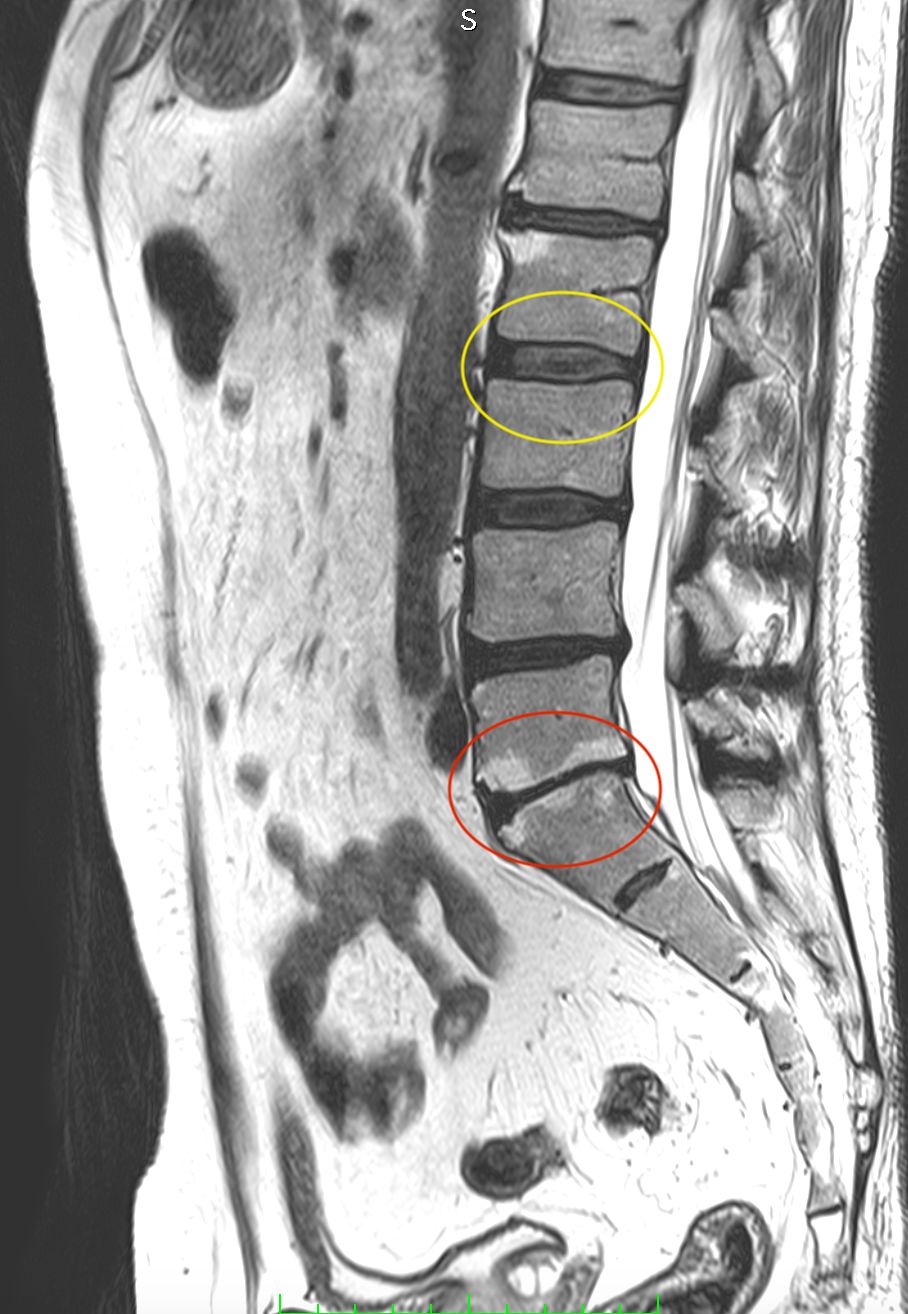

• ernia del disco cervicale, toracica e lombare;

• stenosi del canale vertebrale cervicale e lombare;

• spondilolistesi cervicale e lombare;

• scoliosi degenerativa dell’adulto;

• cifosi degenerativa dell'adulto;